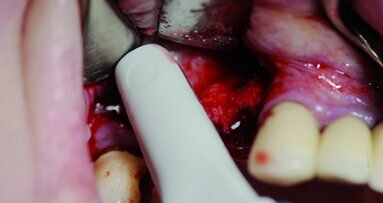

La chirurgie implantaire naviguée peut alors prendre place. Dans ce cadre spécifique, le tracker de repérage du patient est fixé à l’os (vis vertes EDX, X-Nav) et la calibration se fait par le repérage de points osseux par une sonde spécifique (protocole X-Mark ; Fig. 9).

X-Guide est un système de navigation dynamique pour un guidage 3D en temps réel du positionnement des forets sans guide chirurgical. Il est conçu pour améliorer la précision et l’exactitude de la position, de l’angle et de la profondeur de l’implant. Les points de référence sont suivis et affichés en temps réel via deux caméras positionnées entre 60 et 80 cm au-dessus du patient. L’écran guide le chirurgien lors du forage à l’emplacement prévu par le plan d’implant DTX Studio. L’enregistrement virtuel de l’anatomie du patient peut être réalisé avec le protocole X-Mark, ce qui signifie qu’aucun marqueur CBCT n’est requis pour le scan. Trois points sont marqués sur le rendu CBCT dans X-Guide, et les mêmes trois points sont marqués dans la bouche du patient avec une sonde. Pour les cas d’édentements, le tracker de repérage EDX est attaché au patient, dégage la lèvre, et n’interfère pas pendant l’intervention chirurgicale. Il convient à la chirurgie avec ou sans lambeau, et différentes conceptions du tracker de repérage sont disponibles en fonction de la préférence manuelle du chirurgien. Des études ont confirmé une meilleure précision et moins d’écarts par rapport au positionnement prévu de l’implant, par rapport à la chirurgie à main levée.1, 2  Comparé à d’autres systèmes dynamiques testés, X-Guide est trois à quatre fois plus précis.3